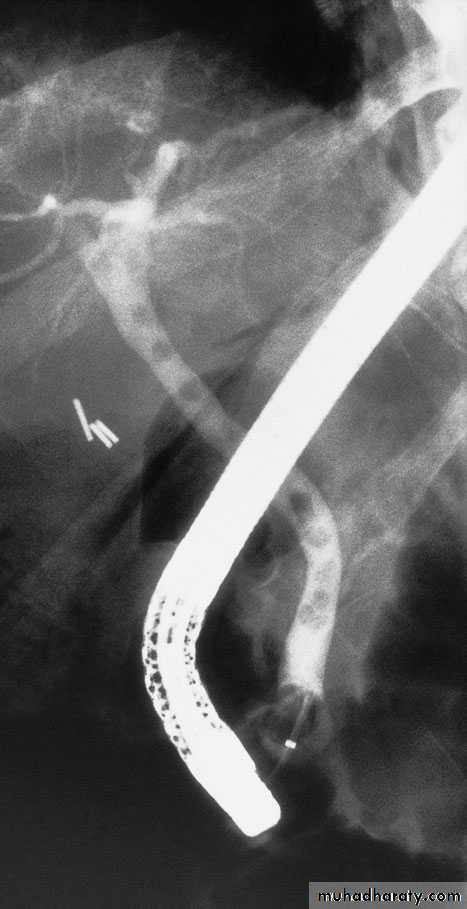

55Endoscopic retrograde cholangiopancreatography: thepatient presented with jaundice 4 days after laparoscopic cholecystectomy.The bile duct contained multiple stones

Al-Madena copy